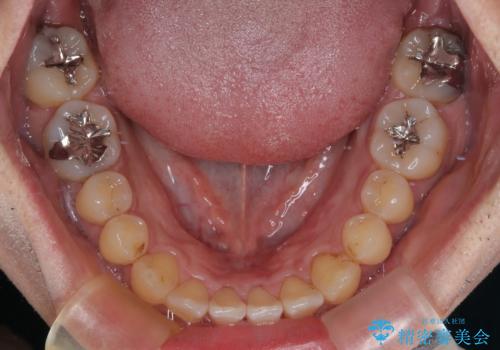

内側に引っ込んだ歯を治したい インビザラインの矯正治療

上下顎ともに歯列全体の側方拡大とIPR(歯と歯の間を削る)によってデコボコとクロスバイトが解消するように設計し、インビザラインにより治療を行うこととしました。

反対咬合特有の治療途中の前歯の干渉が長く続き、治療中に食事をとりにくく、ご迷惑をおかけしました。

前歯の咬み合わせの調整などを行い、安定した咬み合わせに仕上げることができました。